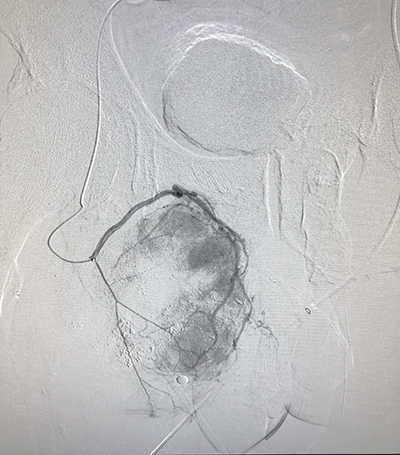

![]() | ![]() |

| (介入术中操作) | (肝癌的介入治疗) |